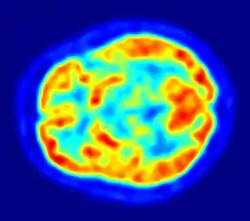

Although the human brain represents only 2% of the body weight, it receives 15% of the cardiac output, 20% of total body oxygen consumption, and 25% of total body glucose utilization.[138] The brain mostly uses glucose for energy, and deprivation of glucose, as can happen in hypoglycemia, can result in loss of consciousness.[139] The energy consumption of the brain does not vary greatly over time, but active regions of the cortex consume somewhat more energy than inactive regions, which forms the basis for the functional neuroimaging methods of PET and fMRI.[140] These techniques provide a three-dimensional image of metabolic activity.[141] A preliminary study showed that brain metabolic requirements in humans peak at about five years old.[142]

Imaging

Functional neuroimaging techniques show changes in brain activity that relate to the function of specific brain areas. One technique is functional magnetic resonance imaging (fMRI) which has the advantages over earlier methods of SPECT and PET of not needing the use of radioactive materials and of offering a higher resolution.[156] Another technique is functional near-infrared spectroscopy. These methods rely on the haemodynamic response that shows changes in brain activity in relation to changes in blood flow, useful in mapping functions to brain areas.[157] Resting state fMRI looks at the interaction of brain regions whilst the brain is not performing a specific task.[158] This is also used to show the default mode network.